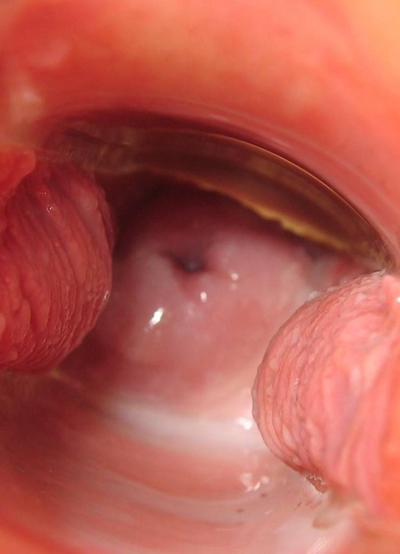

子宮頸癌圖片

宮頸癌

宮頸癌

宮頸癌

宮頸癌

宮頸癌

宮頸癌

宮頸癌

宮頸癌

宮頸癌

宮頸癌

宮頸癌

宮頸癌

宮頸癌

宮頸癌

宮頸癌

宮頸癌

宮頸癌

宮頸癌

宮頸癌

宮頸癌